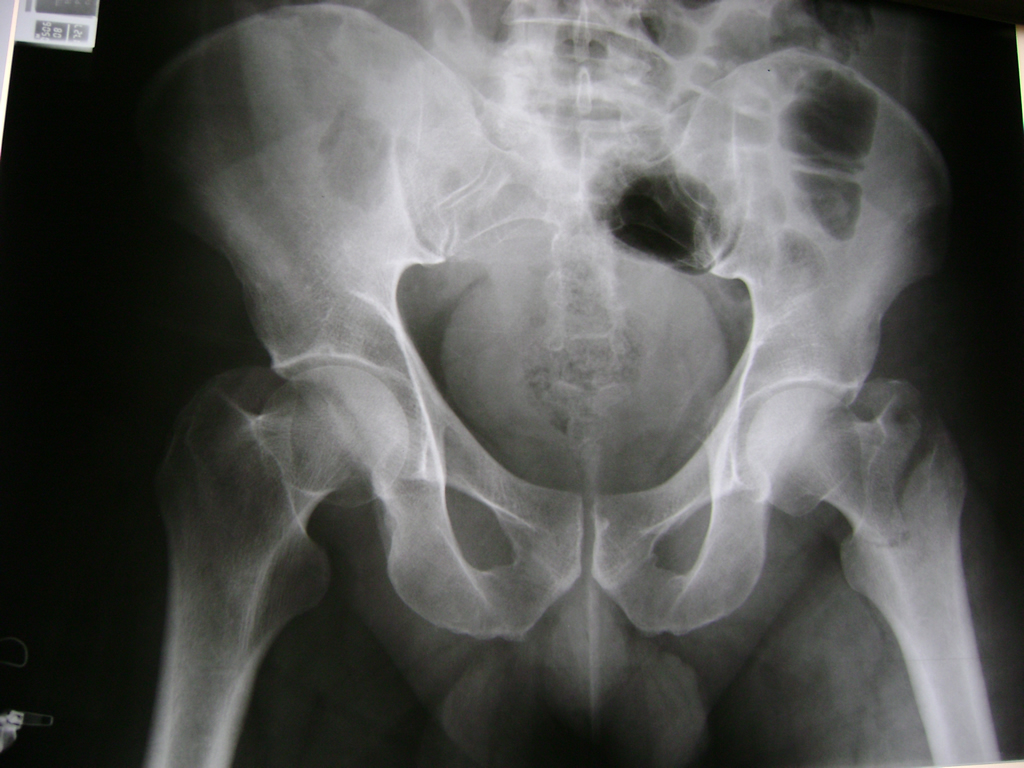

La cirugía de fractura de cadera se realiza para reparar una ruptura en la parte superior del hueso del muslo. Este hueso se denomina fémur.

Es parte de la articulación coxofemoral. Si una fractura de cadera no recibe tratamiento, es posible que deba permanecer en una silla o en la cama.